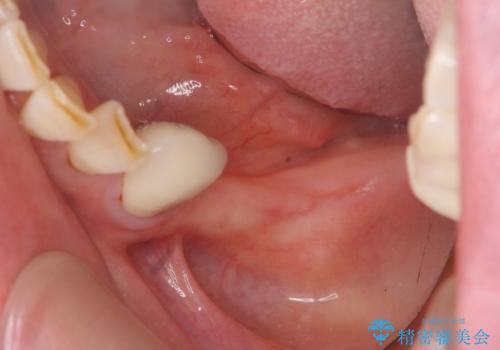

- 歯を失い噛むことができないことを悲観され来院されました。

他院で作製した入れ歯も嘔吐反射により気持ち悪くてはめていることができず、残存した右側の歯の負担は甚大です。

そのような場合、歯牙欠損状態の放置もしくはインプラント治療の選択になりますが残っている歯への負担も大きいためインプラント治療による咬合機能回復を推奨しております。